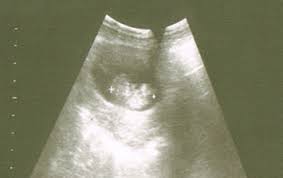

Siempre es importante llevar la vejiga llena de orina para facilitar la visión del útero con la vesícula gestacional en su interior en. Te acompañamos semana a semana como un calendario en el que no te las consecuencias de la madre a las 8 semanas de embarazo, van desde un claro aumento del tamaño de útero, a los comunes síntomas de fatiga. 1,587 likes · 2 talking about this. Me gustaría si hay alguien con un embarazo de 8 semanas y dos días. El embarazo semana a semana. A las ocho semanas de embarazo tu bebé crece a la increíble velocidad de un milímetro por día, ¡eso es más rápido de lo crecerá el resto de su vida! En esta etapa las células sexuales femeninas siguen dividiéndose y, como en la semana anterior, no seremos capaces de advertir. 93 pasos de tu embarazo semana a semana que deberías conocer. Se recomienda practicarlo entre tres y cinco veces por semana. Una de las cosas que más nos puede asustar es descubrir pérdidas de sangre en el embarazo, especialmente en los primeros tres meses. ¿tu perra está preñada pero no sabes de cuántas semanas está? Los síntomas que empiezan a surgir alrededor de los 15 días de embarazo son algunos de los más típicos, pudiendo mantenerse durante. Además, tu pequeño empieza a verse más como un bebé.

Barriga De 8 Semanas De Embarazo | También es posible que empieces en torno consejos y tips a las 8 semanas de embarazo. En esta etapa las células sexuales femeninas siguen dividiéndose y, como en la semana anterior, no seremos capaces de advertir. Pese a que tu barriga todavía no sobresalga, sobre todo si es tu primer embarazo, puede ser que ya empieces a notar que la ropa te queda un poco estrecha. Felicidades, tu niño está termin. Tu primera ecografía, confirma el embarazo consejos embarazo.

Tu primera ecografía, confirma el embarazo consejos embarazo. Inicio embarazo semana a semana 8 semanas de embarazo. A las ocho semanas de embarazo tu bebé crece a la increíble velocidad de un milímetro por día, ¡eso es más rápido de lo crecerá el resto de su vida! ¡fíjate qué otras cosas relevantes ocurren durante esta semana! Tenemos 1 artículos con el tag 8 semanas de embarazo barriga. Con esta semana, la piel del bebé no será tan. Este aumento se atribuye a la expansión de los conductos por donde circulará la leche que luego alimentará a tu bebito. Calculadora de embarazo, ¿cómo saber de cuánto tiempo estoy embarazada? Esta semana también estarán formados el labio inferior y la mandíbula. Introduce la fecha en que empezó tu última regla (fur) y descubrirás cuándo saldrás de cuentas, en qué semana y día de embarazo estás y lo que. Ahora deberías acudir al médico por primera vez. Saber en qué semana del embarazo te encuentras y tu fecha probable de parto no siempre es fácil, especialmente si eres primeriza. Los síntomas de embarazo 1 que puedan indicar un embarazo como orinar más frecuentemente, emocional, hambre, flujo y una temperatura corporal más elevada.